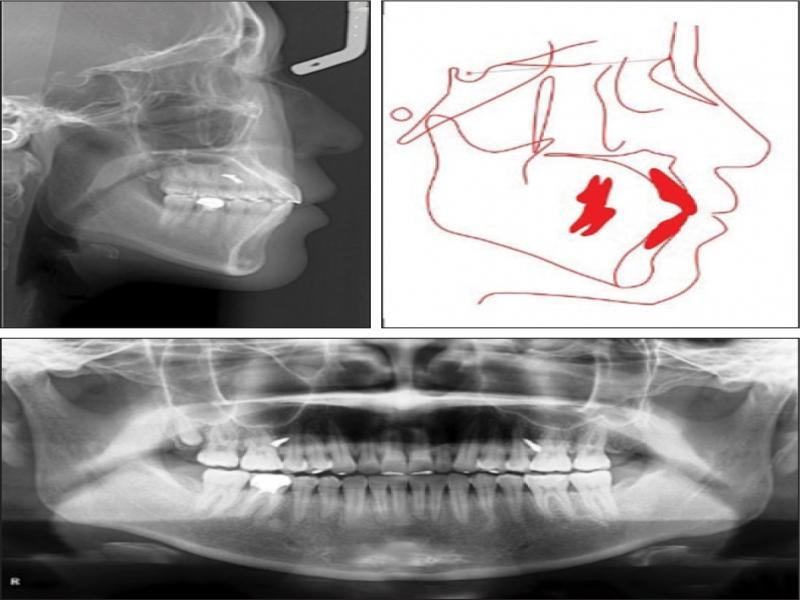

Panoramic radiography showed that the 46 was a crowned tooth with previous root canal treatment. The four third molars were present (Figure 3). A cephalometric analysis indicated a skeletal Class I pattern with an average mandibular plane angle. Both the maxillary and mandibular incisors were proclined (Figure 3).

Pretreatment cephalometric radiograph (top left) and tracing (top right) and panoramic radiograph (bottom).